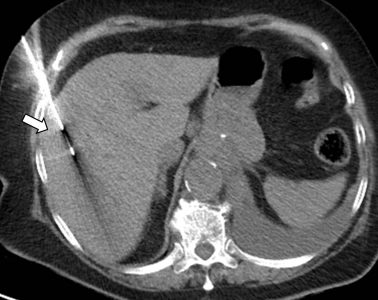

Σε έναν δεύτερο πυλώνα ογκολογικής θεραπείας η Επεμβατική Ακτινολογία μπορεί να εφαρμόσει τοπικοπεριοχική θεραπεία καταστροφής των καρκινικών κυττάρων με τεχνικές είτε διαδερμικής κατάλυσης (Ablation) είτε διαδερμικού ενδαγγειακού χημειοεμβολισμού (TACE). Στην περίπτωση της κατάλυσης μπορεί να εφαρμοστεί σε καρκινώματα του ήπατος, του νεφρού, των οστών και των όγκων μαλακών μορίων και υπό προυποθέσεις στον πνεύμονα. Παθοφυσιολογικά βασίζεται στην τοπική καταστροφή των καρκινικών κυττάρων με τη δημιουργία ιδιαίτερα υψηλών θερμοκρασιών νέκρωσης εντός του όγκου. Αυτό επιτυγχάνεται με τοποθέτηση ειδικών βελονών-ηλεκτροδίων εντός του όγκου υπό ακτινολογική καθοδήγηση. Τα ηλεκτρόδια αυτά παράγουν υψηλή θερμοκρασία είτε με τη βοήθεια ραδιοσυχνοτήτων (RF ablation) είτε με τη βοήθεια μικροκυμάτων (MW ablation) και προκαλούν πηκτική νέκρωση των καρκινικών κυττάρων χωρίς να επηρεάζουν τα φυσιολογικά κύτταρα.

Ο χημειοεμβολισμός είναι μια επικουρική μέθοδος τοπικής θεραπείας για πρωτοπαθή και δευτεροπαθή νεοπλάσματα του ήπατος. Στόχος του επεμβατικού ακτινολόγου είναι η τοπική έγχυση χημειοθεραπευτικού σε κλάδους της ηπατικής αρτηρίας, ώστε να επιτευχθούν υψηλές συγκεντρώσεις τοπικά στην ηπατική εξεργασία χωρίς να προκαλούνται συστηματικές επιπλοκές τοξικότητας του χημειοθεραπευτικού. Επιπλέον, προκαλείται τοπική ισχαιμία-νέκρωση στην περιοχή του όγκου από τα εμβολικά υλικά-μικροσφαιρίδια εμβολισμού, χωρίς να επηρεάζεται το φυσιολογικό ηπατικό παρέγχυμα.

Ο χημειοεμβολισμός έχει καθιερωθεί ως θεραπεία εκλογής στην περίπτωση του ηπατοκυτταρικού καρκινώματος. Ενδείκνυται επίσης σε ηπατικές μεταστάσεις από νευροενδοκρινείς όγκους, καρκίνο παχέος εντέρου και μελάνωμα, σε συνδυασμό με συστηματική χημειοθεραπεία, της οποίας ενισχύει και βελτιώνει τα αποτελέσματα. Ενδείξεις αποτελούν επίσης το χολαγγειοκαρκίνωμα και οι μεταστάσεις από καρκίνωμα νεφρού και σαρκώματα μαλακών μορίων. Οι περισσότεροι ασθενείς μπορούν να επιστρέψουν στο σπίτι τους μία ημέρα μετά τη θεραπεία.